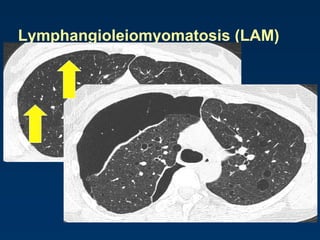

Lymphangioleiomyomatosis (LAM)

HRCT Morphology

Thin-walled cysts (2mm - 5cm)

Uniform in size / rarely confluent

Homogeneous distribution

Chylous pleural effusion

Lymphadenopathy

in young women